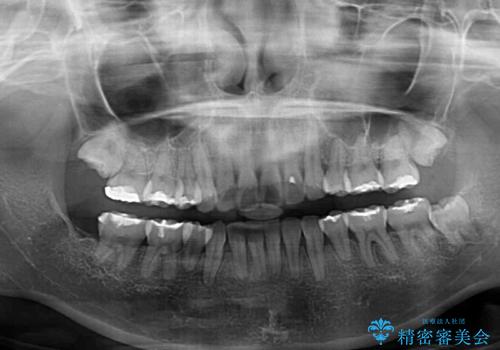

治療後には口が閉じやすくなり、患者様には大変満足していただきました。